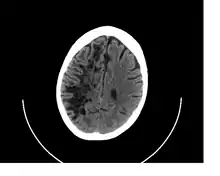

A perivascular space as seen on CT

CT image showing extensive low attenuation in the right hemispheric white matter due to dilated Type 2 perivascular spaces